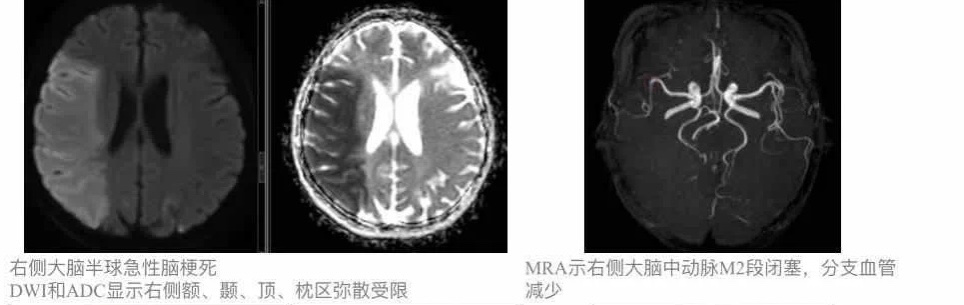

开展的MRI检查项目有:全身磁共振成像平扫及增强扫描,包括:神经系统、头颈部、胸部、乳腺、体部及四肢。磁共振高级功能成像:(1)DWI(弥散加权成像)和ADC(表观扩散系数图):可显示急性、超急性期脑梗塞,鉴别良恶性肿瘤等。(2)TOF法MRA(不打药动脉血管成像):不用注射造影剂,真正无创血管成像,多用于脑部血管病变筛查。(3)MRCP(胰胆管成像):可显示胰胆管扩张情况,常用于胰腺肿瘤和胆道梗阻的诊断。